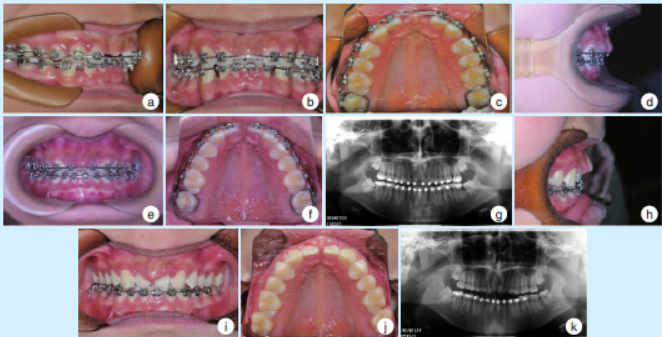

2.2 正畸治疗中(2017 年)

口内检查示:34、44已拔除,近中移动12、22 关闭前牙间隙,内收上下前牙,正面及侧面观,缺牙区龈乳头高度、牙槽间隔高度及宽度未见明显改变(图2a~2c)。

2.3 正畸治疗中(2018 年)

口内检查示:12、22间间隙明显缩小,正面观:上前牙区牙龈垂直向增生覆盖牙面,12、22 临床牙冠变短;腭侧观:12、22腭侧牙龈增生,覆盖12、22舌隆突以上;侧面观:上前牙区牙龈唇腭向增生明显(图2d~2f)。全景曲面断层片示:11、21缺失,12、22近中牙槽骨垂直向明显增生位于牙冠约1/2处(图2g)。

2.4 正畸治疗中(2019 年)

口内检查示:上颌矫治器已拆除,12、22牙间隙未完全关闭,12、22间唇腭侧牙龈及牙槽骨增生明显,缺牙区牙槽骨膨隆,12、22牙龈增生覆盖牙面1/2,色粉红,质地韧。侧面观上前牙区牙龈唇腭向膨隆较前明显(图2h~2j)。全景曲面断层片示:11、21 缺失,12、22 近中牙槽骨垂直向增生较2018 年进一步加剧,充满邻间隙(图2k)。

图2 正畸治疗中患者12、22间唇侧骨性凸起逐渐形成过程的口内照及全景曲面断层片